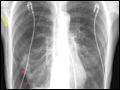

| Figure e34-7 Chest x-ray (CXR) demonstrating right upper lobe collapse (yellow arrow). Note the volume loss as demonstrated by the elevated right hemidiaphragm as well as mediastinal shift to the right. Also apparent on the film are an endotracheal tube (red arrow) and a central venous catheter (black... | |